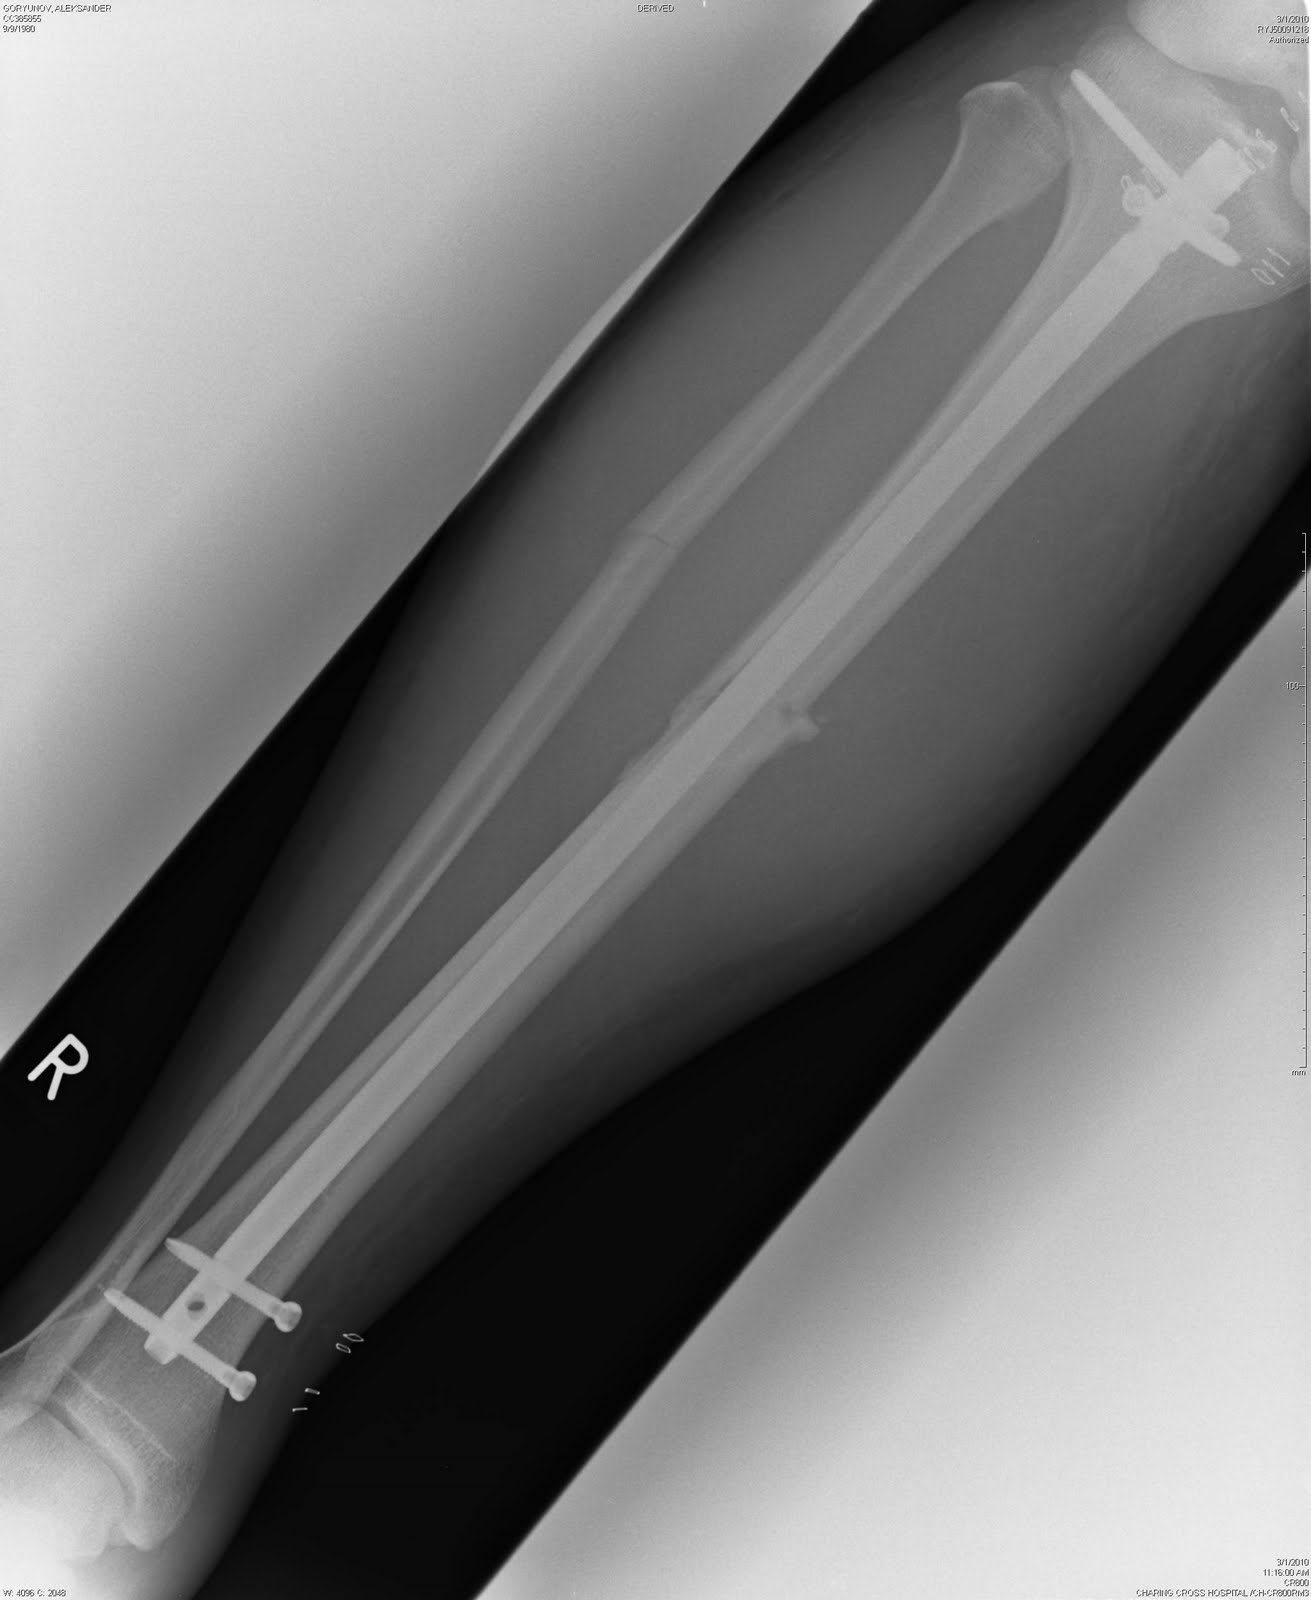

Перелом двойной - тибии и фибулы - закрытый, с клиновидным и сильно смещенным раздроблением тибии. Выглядит все это не очень, так что неудивительно, что мне он показан не был (увижу его только через месяц, когда на CD все рентгены пришлют домой).

Снимок еще раз подтвердил, что мне повезло - гетра с колготками (да, зимой иногда пододеваю к всеобщему смеху колготки - ноги в тепле, проблем с мышцами меньше) каким-то образом удержали ногу после сильнейшего удара и кость не пробилась наружу. Конечно, с другой стороны не повезло - сьехал щиток и оголил ногу в этом месте – но... бывает, а могло быть и хуже.

После изначального вправления, все это стало выглядеть вот так.

Ну, а во время операции под коленом внутрь кости вводят титановый стержень (длина - 40см, диаметр - 12 мм), который фиксируется парой винтов над лодыжкой и парой под коленом. Через год, весь этот металлолом можно вытащить обратно (что я и собираюсь сделать летом 2011-го). Операция нынче достаточно стандартная, только у меня немного осложненная выбитом на колени "клином", так что "ковырялись" в ноге не полтора часа, а три. Без гипса. С некоторыми деталями я уже был знаком - 2 года назад ошибся на выходе и сломал ногу нападающему. У него перелом был "чище" моего. А мне - карма. Результат вот такой.